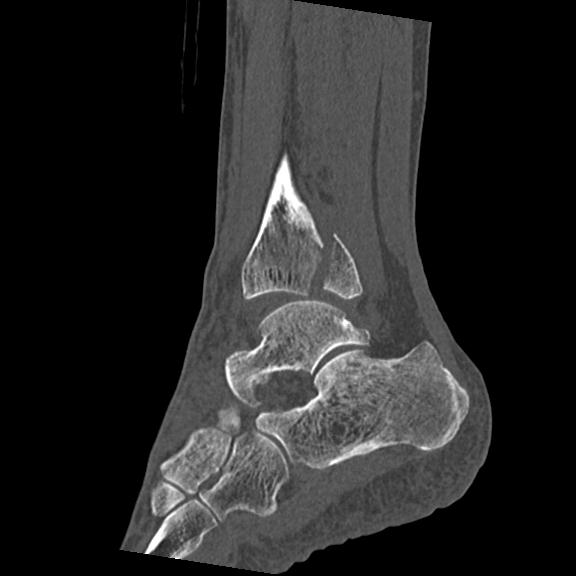

56476 8/28 4R 1/21 2R 左足関節 デジカメ写真 72歳女性 右足関節AS